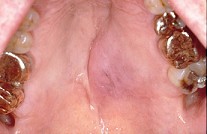

2.下列關(guān)于黏液表皮樣癌(如圖)的敘述,不正確的是  (    )